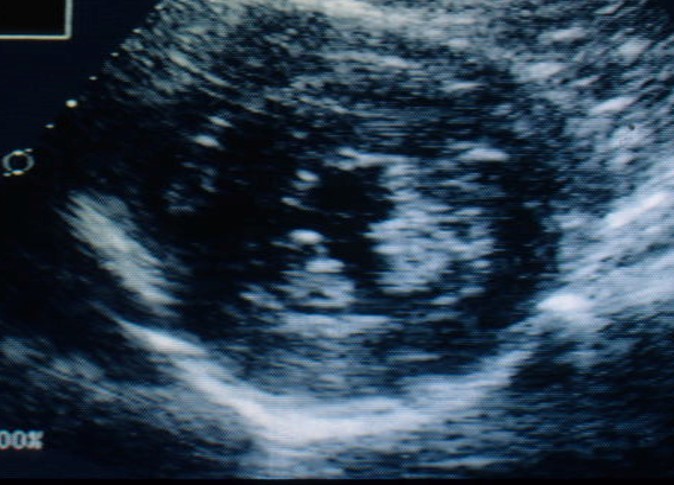

What does this show?

A short-axis

(cross sectional)

view of the L ventricle shows a thick LV free wall and a thick interventricular septum with a small ventricular lumen